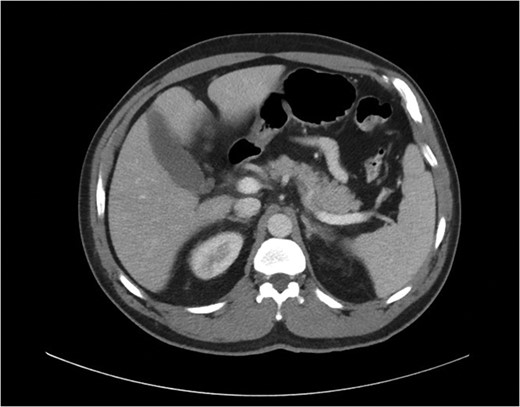

Biopsy of the affected organ is the only way to confirm the diagnosis of intravascular lymphoma. The predominant microscopic finding of IVLBCL is atypical blastoid cells with multiple mitoses that exclusively proliferate within vascular and sinusoidal structures of the organ. Mouse xenograft models have indicated that inhibition of cell migration may be involved in IVLBCL pathogenesis and may account for the limited growth locations within the host [5]. Immunohistochemical staining is positive for B-cell markers CD19, CD20, CD22 and CD79a in the absence of staining for T-cell markers [1, 6, 7]. On imaging, both primary and secondary hepatic lymphomas show mild enhancement after contrast administration including a homogeneous and rim-like pattern, and central necrosis may produce a heterogeneous appearance. Most patients with primary or secondary hepatic lymphomas also present with associated lymphadenopathy, whereas patients with IVLBCL frequently have neither central necrosis nor lymphadenopathy, presentations that may aid in differential diagnosis of IVLBCL from other forms of hepatic lymphomas [7].